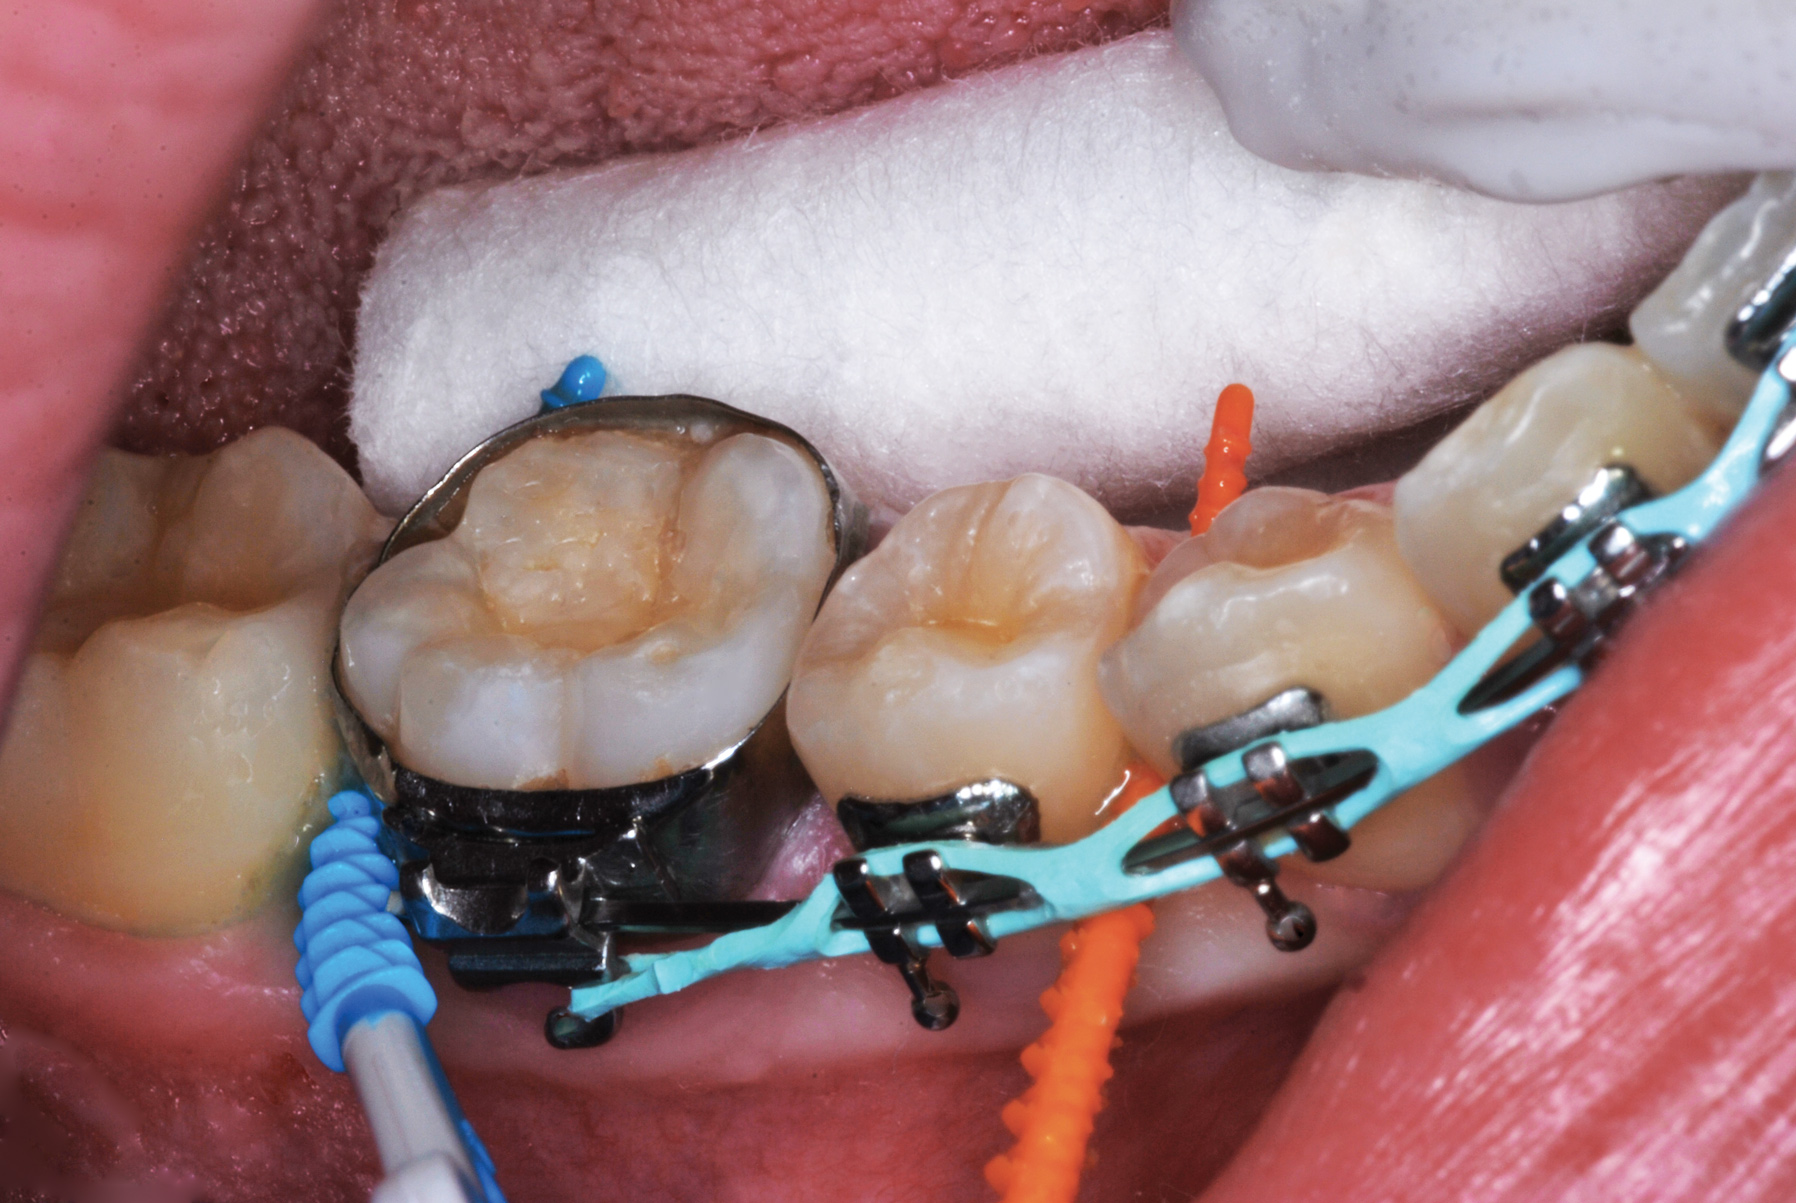

The authors' protocol for insertion of SDF-coated soft dental picks involves isolating the teeth with cotton rolls or other means, flossing the interproximal site to clear food debris and dental plaque, and then inserting a SDF-coated pick (Figure 1 and Figure 2) to saturate the contacting surfaces of the teeth with the fluid. This treatment is painless and requires no anesthetic. The pick should remain in place for at least 60 seconds and can be gently pulled in and out to agitate the fluid for enhanced surface coverage by capillary action. Additional SDF can be wiped on, using a small applicator, above the contact and in the buccal and lingual sluiceways. Excess fluid and any blood elicited may be blotted with a cotton swab. An additional 60-second insertion may be applied in the same way if there is radiographic evidence of a deeper decalcification or caries lesion. With the pick still in place, 5% (or 2.5%) fluoride varnish is painted over the treatment area, and the pick is then withdrawn.

Interproximal insertion of SDF is demonstrated in different patients in Figure 3 through Figure 11. Various diameters and brands of soft dental picks may be used depending on the closeness of the proximal surfaces and ease of insertion; for example, some picks are designed for use in wider spaces between teeth. This protocol also offers versatility. Figure 3, for example, shows the simultaneous use of three thin soft dental picks to saturate proximal surfaces with SDF in a teenaged patient; the treated regions were subsequently covered with fluoride varnish (Figure 4). This patient was initially treated in April 2019 (Figure 5), with an identical re-application 3 months later. As shown in Figure 6, the December 2019 bitewing film revealed good results with the possible exception of the contact regions of the maxillary first and second molars. New SDF application was completed in the December appointment.

Figure 7 illustrates the use of thicker picks in premolar interproximal sites. Additionally, multiple picks can be used in one quadrant or in one proximal site with good isolation to maximize fluid saturation (Figure 9), which the authors have found to be an excellent time-saving strategy. Preventive or interceptive applications of SDF may also be effectively used in interproximal sites in orthodontic patients (Figure 10).

Fig 10. Interproximal sites in orthodontic patients can also benefit from preventive or interceptive SDF applications.

Figure 10